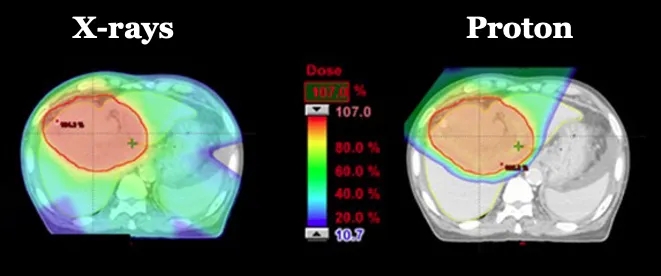

安全性数据表现优异:47例患者(92%)仅出现1级及以下急性肺毒性,仅3例为2级、1例为3级,无4级及以上急性肺毒性发生,且患者远期毒性反应极少。此外,既往研究针对局部晚期NSCLC患者的剂量分布分析也证实了质子治疗的安全性优势——与调强光子放疗(IMRT)相比,质子治疗对危及器官(OAR)的剂量显著更低:传统IMRT易使辐射波及肿瘤周围健康组织(详见下图左),而质子疗法可将大部分辐射精准集中于肿瘤靶区(详见下图右)。

▲图源“Trials”,版权归原作者所有,如无意中侵犯了知识产权,请联系我们删除